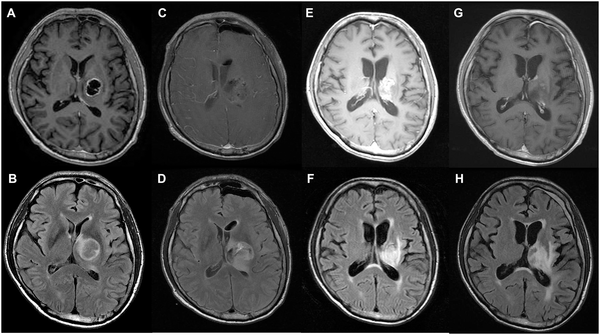

一名52岁女性,因神志不清、复视、运动无力入院。术前磁共振成像(MRI)显示:下丘脑病变中的囊性和实性肿块。术后MRI显示T1增强图像上的肿瘤次全切除(C、D)。在一年的随访MRI中,T1-对比增强图像(E)有不规则增强,T2-FLAIR图像(F)有高信号。在2年的随访MRI中,T1增强(G)和T2-FLAIR图像(H)显示稳定状态。患者健在,术后生存时间为1469天。